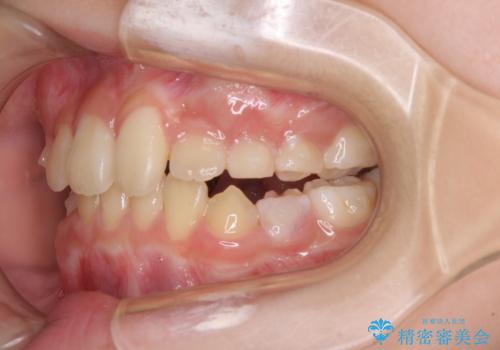

- 前歯の叢生を気にして来院された、小学校3年生女児の患者様です。

身長がやや低く、乳歯から永久歯への交換が少し遅い印象があったので、ワイヤー装置による1期矯正治療ではなく、乳歯も積極的に動かすことのできるインビザライン・ファーストにて治療を行うこととしました。

上顎前歯に過剰歯があったため、まずはその歯を抜歯し、傷が治癒したタイミングでインビザラインを発注することとしました。